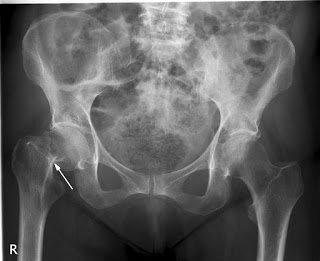

Eficacia de un programa poblacional de rastreo de osteoporosis en mujeres de 70 a 85 años

Se calculó el puntaje FRAX y se realizó densitometría a aquellas con riesgo de fractura elevado, dejando el tratamiento a criterio del médico de cabecera. Se logró una reducción del 28% (IC 11-41%) de las fracturas de cadera. The Lancet, 15 de diciembre de 2017